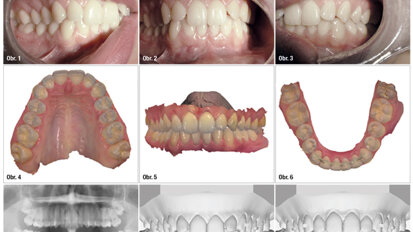

Hybridní terapie alignery